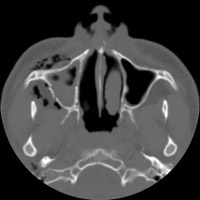

- Click on the image for a larger versionBAxial CT. This image through the maxillary sinuses confirms the presence of subcutaneous gas.

- Click on the image for a larger versionCAxial CT. This image through the maxillary sinuses reveals a fracture of the lateral wall of the right maxillary sinus, the source of the emphysema